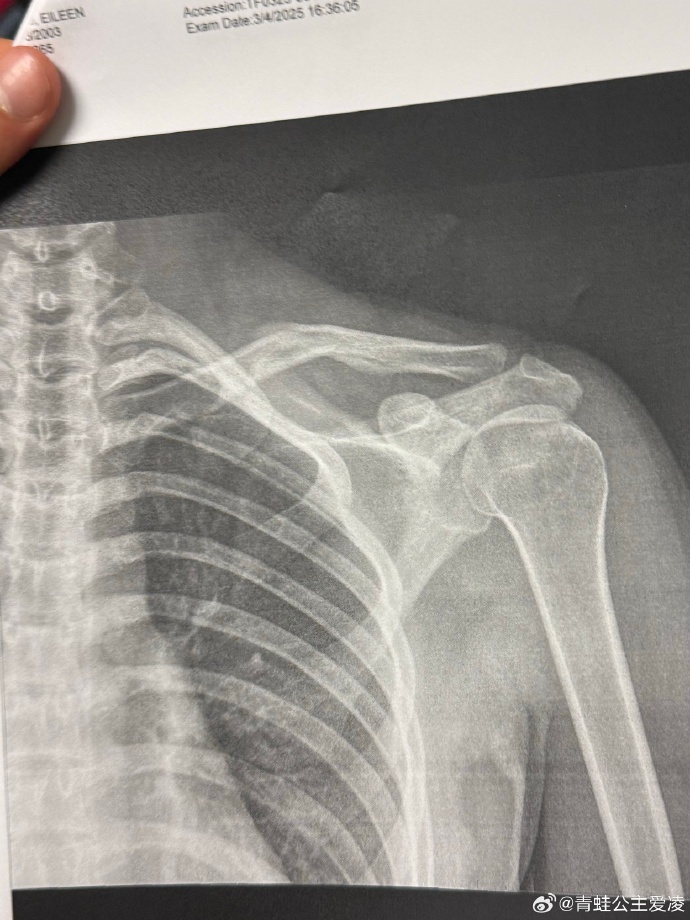

3月9日,谷爱凌在社交媒体晒出肩部骨折的X光照片,并配上一个心碎的表情,X光照片显示的日期是3月4日,目前尚不得知谷爱凌本次的伤病是新伤还是旧伤。